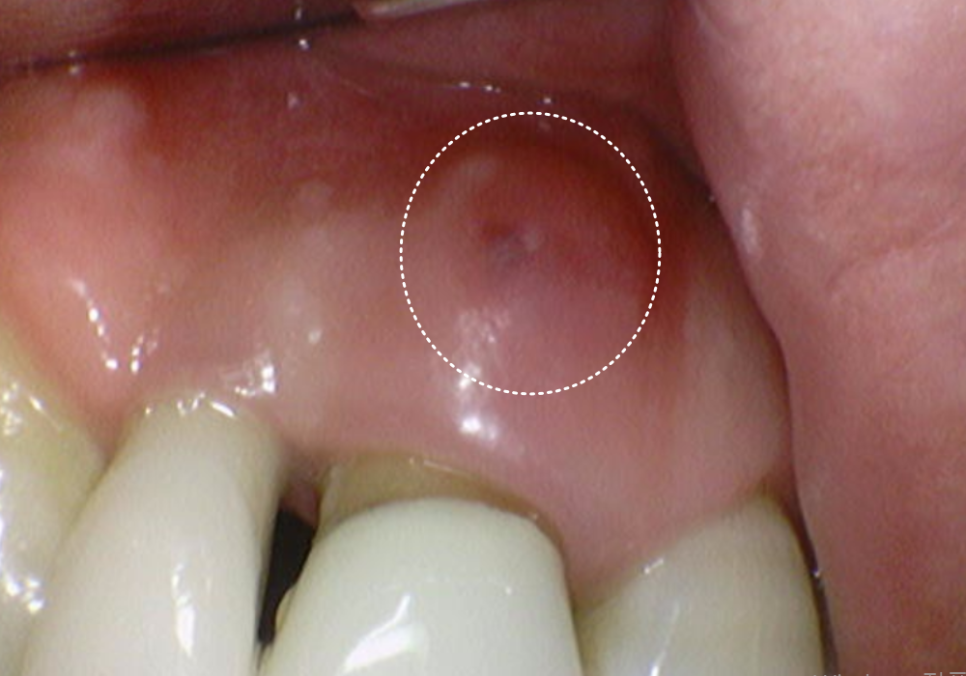

환자분께서 중앙 앞니(#11)가

잇몸이 부었다가 가라앉기를 반복한다며

다시 내원하셨어요.

251125

자세히 살펴보니 고름이 빠져나온 흔적이 보이네요.

흔들림도 이전보다 심해진 상태였습니다.

C뿌리 끝 염증도 더 심해진 상황...

안타깝지만 이 치아도 발치 후

임플란트로 재건하기로 결정했습니다.